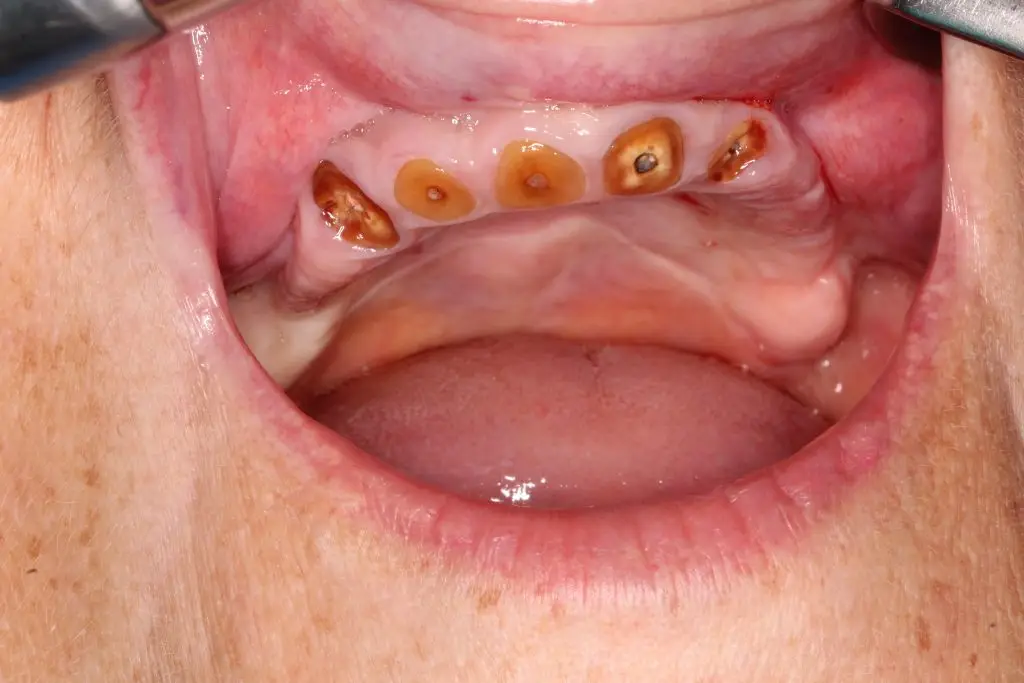

Pacienta avea o lucrare veche, dinti cu infectii si distructii coronare impirtante ce nu puteau fi restaurati. Era nemulțumita de aspectul lor și își pierduse încrederea în zâmbet.

Am recomandat extractia dintilor irecuperabili, aditia osoasa si procedura all on 6.